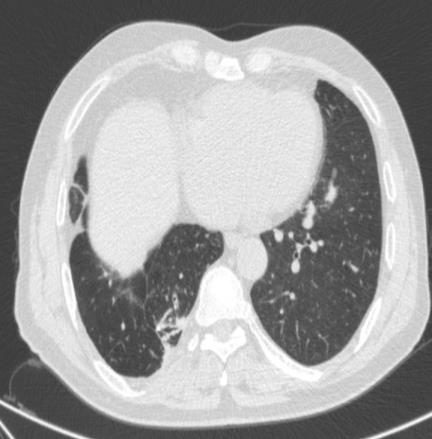

• 获得性免疫缺陷综合征合并马尔尼菲篮状菌导致肠道感染的内镜下表现(附6例报告)

2026, 32(3):84-88. DOI: 10.12235/E20250461

摘要 (32) HTML (27) PDF 3.50 M (26) 评论 (0) 收藏

摘要:目的 探讨获得性免疫缺陷综合征(AIDS)合并马尔尼菲篮状菌(TM)感染导致肠道感染的内镜下特征。方法 回顾性分析2022年11月-2024年10月于该院确诊为AIDS合并TM感染导致肠道感染的6例患者的临床资料。包括:临床症状、实验室检查、影像学检查、内镜检查和病理检查等。结果 6例患者中,男5例,女1例;发病年龄26~67岁;AIDS合并TM感染导致肠道感染患者的临床表现为:腹泻、腹痛、腹胀和恶心呕吐。其中,2例有消化道出血表现。实验室检查:6例患者外周血白细胞计数为(1.37~4.49)×109/L,血红蛋白计数为(67~99)g/L;CD4+T淋巴细胞为(1~52)个/μL,CD8+ T淋巴细胞为(61~321)个/μL,CD4+T淋巴细胞/CD8+T淋巴细胞比值为(0.01~0.18)。6例患者均行HIV RNA检测。其中,5例HIV RNA阳性。血培养:可见丝状真菌,报告显示为TM。影像学检查:6例患者CT结果可见肠系膜及腹膜后多发淋巴结肿大。内镜检查:6例患者内镜下均可见肠道病变。其中,十二指肠糜烂溃疡2例,结肠多发糜烂溃疡4例。病理检查:6例患者幽门螺杆菌(Hp)结果均为阴性,黏膜下可见成簇的小球形真菌孢子,符合TM感染;特殊染色:PAS(+),六胺银染色(+)。结论 当AIDS晚期患者出现消化道症状时,应警惕TM感染,病变部位常见于全结肠和直肠,亦可累及十二指肠,内镜下表现多为溃疡、糜烂和隆起性病变,形态表现无特异性;及时行胃肠镜检查、病理活检、特殊染色和免疫组化是确诊的关键。